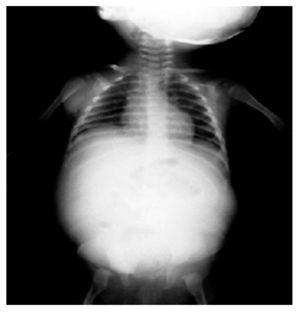

A su ingreso se reportó una creatinina sérica de 6.22 mg/dL, urea de 141 mg/dL, BUN 66 mg/dL, leucocitos de 26.2, hemoglobina de 7.44 g/dL. Se realizó un ultrasonido abdominal y una tomografía axial computada de abdomen, en los cuales se logró observar una fusión renal con presencia de ectasia de cavidades renales, y la pérdida de la continuidad del parénquima renal, así como la presencia de gran cantidad de líquido libre perirrenal sugestivo de un urinoma (Figura 2).

Figura 2. A) Ultrasonografía renal que muestra dilatación de cavidades. B) TAC corte axial en el que se observa périda de la continuidad del parénquima renal y líquido libro perirrenal. C) TAC corte coronal en el que se observa fusión renal con gran cantidad de líquido libre.